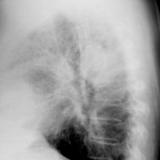

Bronch Cyst 1  Lat

Date: 05/11/2004

Views: 6781